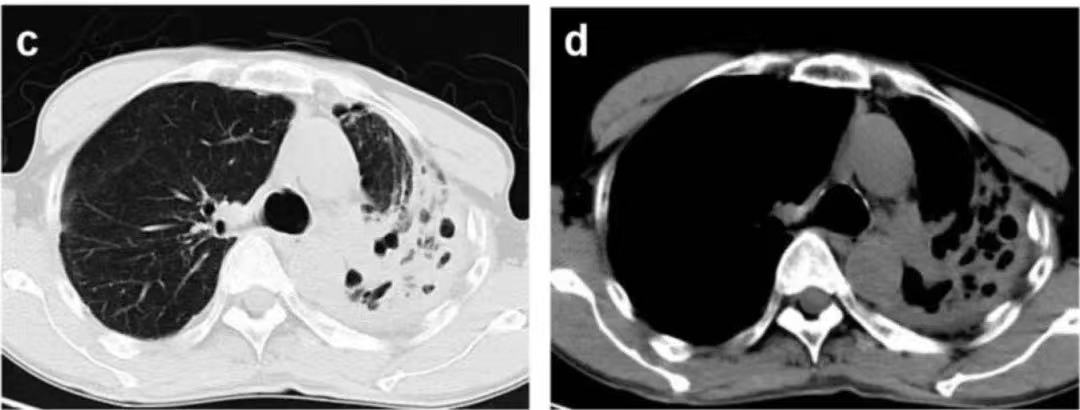

ÐØ²¿CTÏÔʾ×ó·ÎÉÏÒ¶ÓÐÂýÐÔѬȾºÍÊÜËð²¡Ôî

¡°·Î²¿CT¿´ÆðÀ´²»ÏñÊǷνáºË¡£¡£¡£¡£¡£¡£¡£¡£ÎÒÃÇÖØ¸´ÁôÁËÐí¶à´Î̵ͿƬ¶¼Ã»ÓÐÕÒµ½½áºË¸Ë¾ú£¬£¬£¬ £¬£¬ £¬ÈôÊÇÊǽáºË·ÖÖ¦¸Ë¾ú»ò·ÎÇúù¾ú£¬£¬£¬ £¬£¬ £¬²»Ó¦ÔÆÔÆ·´Öظ´¸´¡¢¿ØÖƲ»×¡£¡£¡£¡£¡£¡£¡£¡£¡¡±ÖÜ»ªÖ÷ÈÎÌåÏÖ¡£¡£¡£¡£¡£¡£¡£¡£Æ¾Ö¤¸»ºñµÄÁÙ´²ÂÄÀú£¬£¬£¬ £¬£¬ £¬Ëû³éÈ¡ÁËÖ§Æø¹Ü·ÎÅݹàÏ´Òº(BALF£©ËÍÍùÁÙ´²Î¢ÉúÎïÊÒ×÷Óý¡£¡£¡£¡£¡£¡£¡£¡£